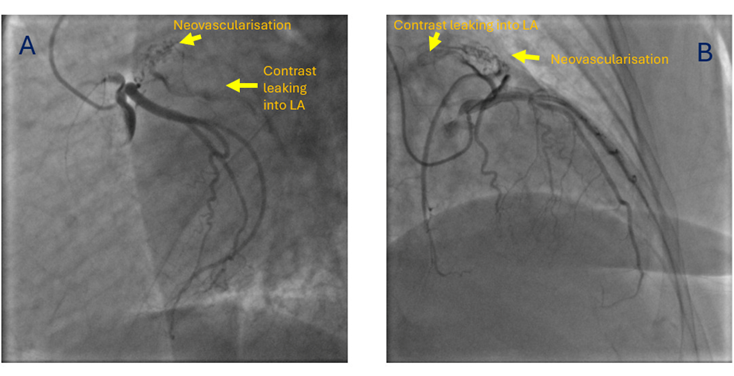

She was taken up for a preoperative coronary angiography with a plan for a subsequent mechanical mitral valve replacement. The coronary angiogram revealed normal epicardial coronary arteries. However, the atrial branch of the left circumflex artery was seen giving small branches to a left atrial appendage (LAA) clot (neovascularization), with contrast leaking into the left atrium (LA) from these neovessels (Figure, Video). A transesophageal echocardiogram later confirmed the LAA clot. The patient was subsequently planned for a mechanical mitral valve replacement and LAA clot removal.

In a previous study from our center, which included 81 patients with rheumatic mitral stenosis, angiography predicted thrombosis by demonstrating neovascularity, manifesting as a bunch of small vessels arising from the circumflex branch of the left coronary artery and terminating in a network of smaller vascular channels, with a blush of contrast medium consolidating into small lakes.1 For recognizing thrombi in the LA or LAA, selective left coronary angiogram demonstrated sensitivity and specificity of 72.7% and 92.7%, respectively, and an 88.8% predictive value.1